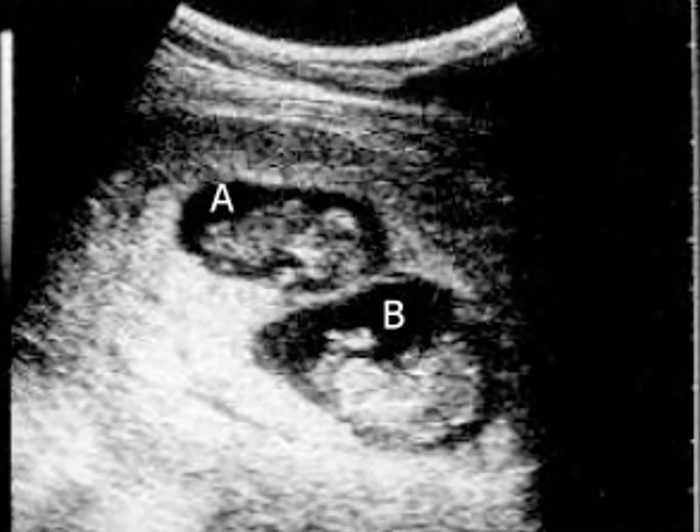

What type of pregnancy?

dichorionic pregnancy